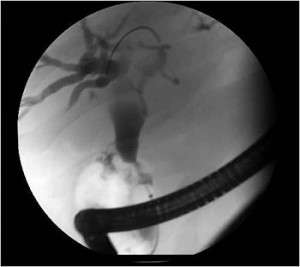

Image courtesy of Shawn Mallery, MD, and Minnesota Pancreas and Liver Center

Endoscopic retrograde cholangiopancreatography (ERCP) is a procedure used to get pictures of the digestive tract, including the pancreas. It takes X-ray pictures after a dye is injected through a thin tube. Doctors may use this imaging test to diagnose pancreatic cancer or to treat its symptoms.

During an ERCP, patients lie on their side. The doctor passes a thin, lighted tube, called an endoscope, through the patient’s mouth, esophagus and stomach and into the small intestine. The patient can breathe normally.

The doctor puts a narrower plastic tube, called a catheter, through the endoscope. Then the doctor adds a contrast dye, a substance that helps doctors see inside a patient’s body more clearly, through the catheter and takes an X-ray picture.